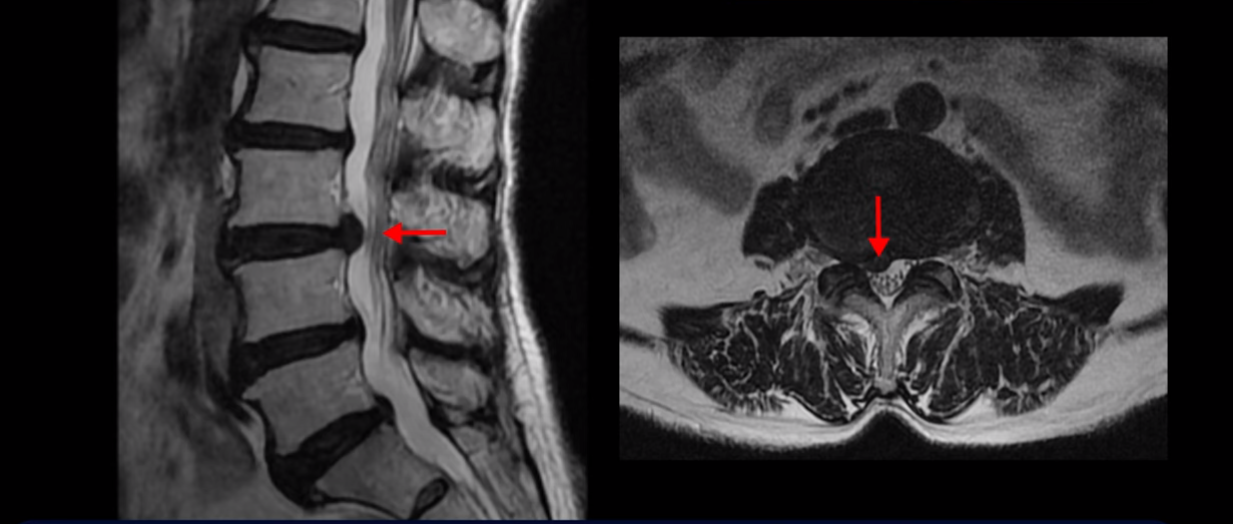

먼저 이분 MRI 보면서 간단히 설명 드린 후 어떻게 신경이 눌려서 수술해야 된다는 환자를 수술 없이 치료할 수 있는지 또 치료는 어떻게 하는지 자세히 설명 드리겠습니다. 이분 허리 MRI를 보면 여러 마디가 퇴행되어 있고

3번 4번 마디에 디스크 파열이 있습니다.

하지만 이 디스크 파열은 오래된 걸로 보이며, 지금 이 환자분의 아픈 양쪽 다리 특히 양쪽 발의 통증, 발 시린 증상과는 관련이 없어 보입니다. 오른쪽 왼쪽의 신경가지가 빠져나가는 추간공을 보면 오른쪽은 5번 1번과 4번 5번이 많이 좁아져 있고

왼쪽은 5번 1번이 많이 좁아져 있습니다.

이렇게 오른쪽 왼쪽 양쪽 추간공들이 다 좁아져 있고 신경가지들이 눌려있으니까 양쪽다리와 양쪽 발이 저리고 시리고 아파서 걷기 어렵습니다. 그런데 이 환자분은 신경주사를 여러 번 맞아도 듣지를 않는데요. 이렇게 신경주사가 듣지 않으면 십중팔구 수술밖에 방법이 없다는 얘기를 듣습니다. 그럼 어떻게 이런 신경이 눌려있는 환자분들을 수술 없이 치료해서 잘 걷게 만들고 다리와 발이 저리고 시리고 아픈 증상이 사라지게 만들까요? 지금부터 설명해드립니다.